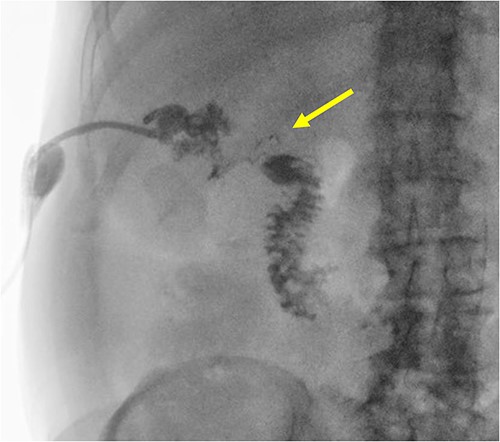

The patient is a 63-year-old male who underwent laparoscopic cholecystectomy with intraoperative cholangiogram for symptomatic gallstone disease at an outside hospital 2 years prior to our initial visit. His postoperative course was complicated by biloma and retained gallstones in the common bile duct, for which he underwent endoscopic biliary sphincterotomy 4 months after the initial surgery. His medical history was notable for alcoholic cirrhosis with a Model for End-Stage Liver Disease score of 14, duodenal ulcers, and gastric angiodysplasia. Symptoms included intermittent abdominal discomfort, nausea, and vomiting 1 year after the cholecystectomy. Computed tomography (CT) showed a perihepatic abscess measuring up to 7.5 × 5.1 cm, containing gallstones and punctate free-air near the right hepatic lobe (Fig. 1). He underwent image-guided percutaneous drainage of the hepatic abscess. A fistulogram via the abdominal drain demonstrated communication between the abscess cavity and the second segment of the duodenum, confirming the presence of a duodenal-perihepatic fistula, feeding the abscess cavity (Fig. 2). Interestingly, the oral contrast administered during a prior abdominal CT scan did not demonstrate this fistulous connection. The patient underwent endoscopic closure of the fistula using an over-the-scope clip device (Fig. 3). Repeat CT 2 months following the closure showed that the perihepatic abscess decreased in size with no evidence of a new abscess. On initial follow-up, the patient demonstrated clinical improvement in his overall health. Continued follow up revealed near complete resolution of the perihepatic abscesses and continued clinical improvement.

A radiographic fistulogram demonstrating the fistulous tract communicating with the second part of the duodenum.